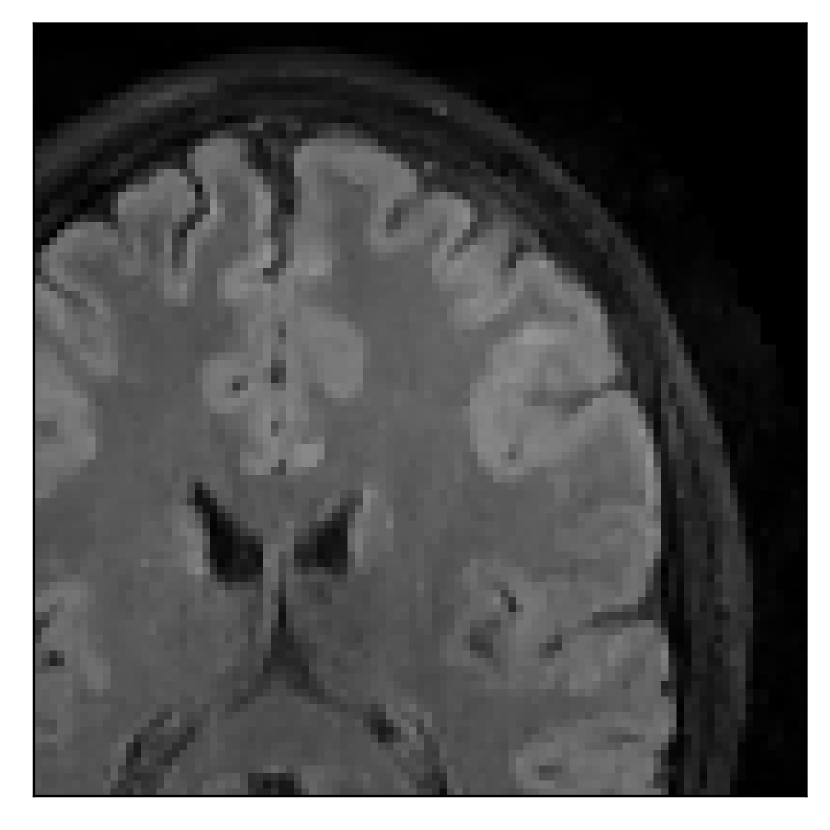

3.2 Experiment 2: on the choice of the reference contrast

This in-vivo experiment tests the proposed correction scheme with respect to a different combination of corrupted and reference contrast, namely a T1-weighted corrupted contrast with a T2-weighted reference contrast (see Table 1). For this experiment, we prompt volunteer 2 to move five times during the acquisition. The corrupted acquisition employs randomized sampling.

In Section 4.2, we gather the results for this experiment.

4.2 Experiment 2: choice of the reference contrast

With the experiment described in Section 3.2, we demonstrate the flexibility of the correction scheme with respect to the choice of the reference contrast. The results are shown in Figure 10. Contrary to the experiments detailed in the previous section, we are now considering a T2-weighted reference contrast to guide the correction of a T1-weighted corrupted contrast. The quality of the correction indicates that the proposed technique is rather flexible in terms of reference contrast.